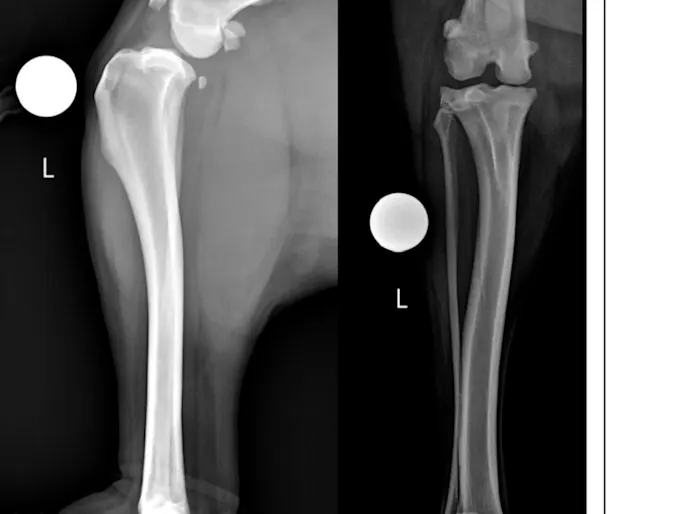

Franki: Gunshot Case

Surgery

Franki was out on a walk with her owner when she was shot by a hunting rifle from approximately 100 yards away.